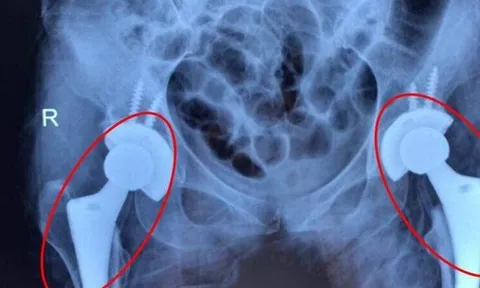

Nhiều người trẻ bị mục xương vì chất kích thích ai cũng dùng

Tắc mạch máu diễn tiến âm thầm khiến nhiều bệnh nhân bị mục cả 2 khớp háng, đối mặt nguy cơ tàn phế. Bác sĩ cảnh báo, nguyên nhân dẫn tới tình trạng trên là do người bệnh lạm dụng rượu bia. Giải pháp để cứu bệnh nhân là thay cả 2 khớp háng.